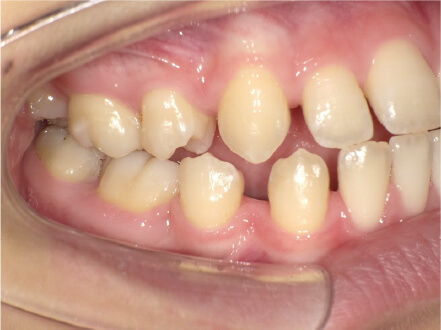

叢生の症例

11歳

/

女性

相談内容

上の前歯の歯並びが気になる(マイオスマイルからの移行)

カウンセリング・診断結果

インビザライン、拡大入れながらスペースを作成、下Eは出てきたら削りながら進める

治療内容・方法

全額アライナー矯正 クリアコレクト

術後の経過・現在の様子

クリアライナー使用

治療のリスク

痛み・歯根吸収・歯肉退縮・虫歯・後戻り

費用・治療期間

移行料金220,000円、月々16,500円、1年1ヶ月+myo2年3ヶ月